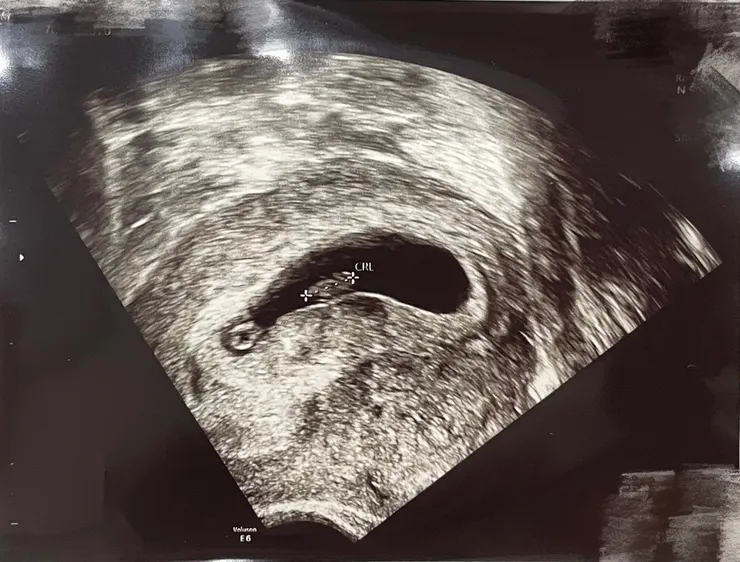

第六週,約了排程是照超音波的時間,主要也是看看胎兒的心跳是否正常!

從檢查人員口中得知,機器設備除了檢查位置外,也有偵測到心跳的訊息,

但是不會另外播放“蹦蹦蹦蹦”胎兒的心跳聲給我聽

等週數稍大一些,說明醫生會在後續檢查時才會聽到

超音波拍起來乍看之下很像一隻炸蝦XD

進入懷孕第六週,胚胎(Embryo)在子宮內膜中繼續生長,長度為 0.6 公分,可以說是一顆蘋果籽的長度,形狀則像是個小蝌蚪。寶寶的心跳也有機會在陰道超音波檢查時可以確認到。

第六週胎兒超音波圖/Ching